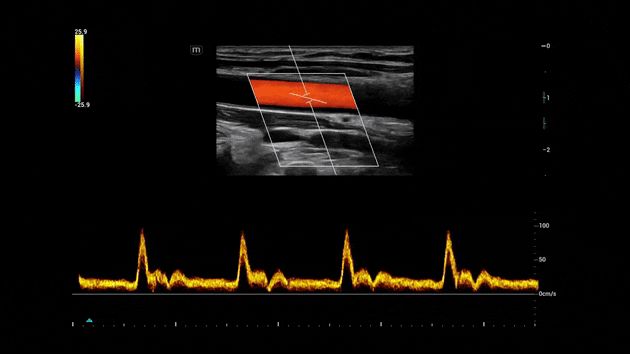

Consona presenta soluzioni nuove e concrete, che aiutano a effettuare diagnosi efficaci con semplicitĂ , rivolgendosi a un'ampia platea di pazienti. La serie mette a disposizione strumenti estremamente avanzati per rimanere all'avanguardia nella diagnosi cardiovascolare.

Galleria di immagini